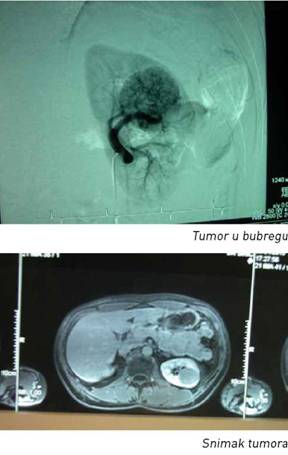

U traganju za uzročnikom hematurije, ultrazvučni (UZ) pregled urinarnog trakta je, uz neophodne laboratorijske analize, prva i veoma dragocena dijagnostička procedura. Ultrazvučnim pregledom mogu se otkriti tumorske promene na zidu mokraćne bešike, na bubregu, u kanalnom sistemu (pijelonu ili ureteru). Ističući veliki dijagnostički značaj ultrazvučnog pregleda, prof. Lazić kaže da iskusni doktori već uz pomoć UZ mogu da detektuju tumor u bešici veličine četiri do pet milimetara. Čak i kad se tumorska promena ne vidi direktno, a UZ pregled pokaže zastoj mokraće koji indirektno ukazuje da na njenom putu postoji prepreka, pri totalnoj bezbolnoj hematuriji se takođe može sumnjati na tumor.

Ukoliko UZ ne otkrije uzrok hematurije, obavljaju se rendgenska snimanja kojima se proverava eventualno prisustvo kamenčića u urinarnom traktu. Intravenska pijelografija je kontrastno rendgensko snimanje koje takođe može da pokaže tumorsku promenu, u mokraćnim putevima, mokraćnoj bešici ili u bubregu. Ukoliko je potrebno, ovaj dijagnostički niz može se dopuniti skenerskim pregledom. Multislajsni skener, naime, omogućava takozvanu MSCT urografiju, koja bolje prikazuje strukturu bubrežnog parenhima i okolinu mokraćnih puteva, kao i same mokraćne puteve. Magnetna rezonanca je, prema rečima prof. Lazića, retko potrebna kao dodatna dijagnostička procedura.